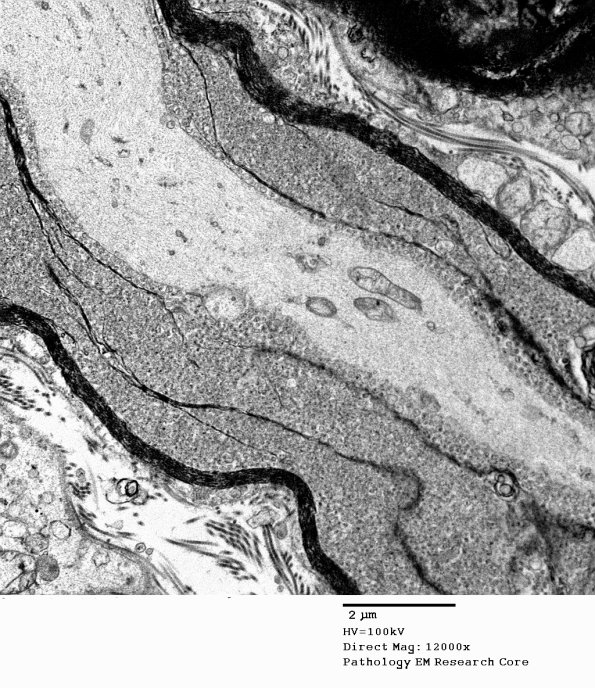

19C5 Artifact, vesicular myelin, spinal root EM 032A - Copy

Higher magnification of image #19C4. (electron micrograph)